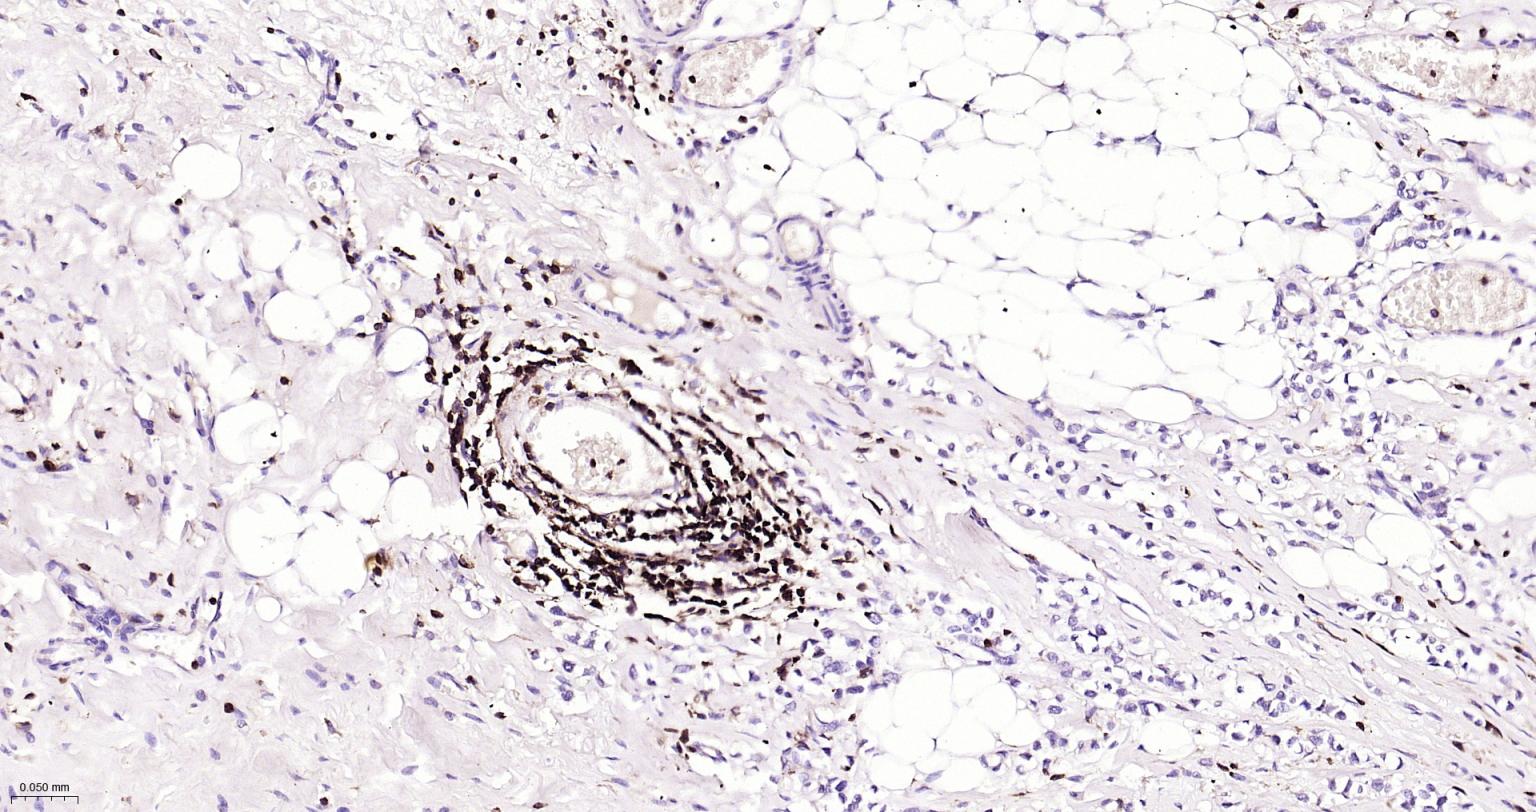

Paraformaldehyde-fixed, paraffin embedded Human Ovarian Cancer; Antigen retrieval by boiling in sodium citrate buffer (pH6.0) for 15 min; Antibody incubation with CD45 Monoclonal Antibody, Unconjugated(bsm-54757R) at 1:200 overnight at 4°C, followed by conjugation to the bs-0295G-HRP and DAB (C-0010) staining.